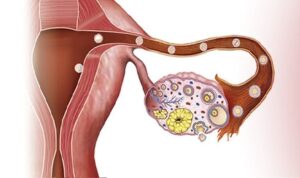

¿Qué es un embarazo ectópico? Un embarazo ectópico es un embarazo que ocurre fuera de [...]